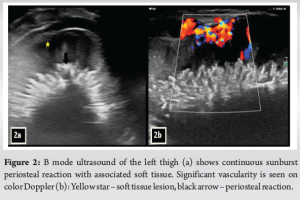

A 3-year-old female was brought to the pediatric orthopedic department with complaints of swelling over her left leg for 2 months. The swelling was insidious in onset, progressive in nature, associated with pain which was aggravated by movement, more at night, and associated with fever and local rise of temperature. According to the mother, weight loss and loss of appetite were noted. No history of abdominal pain. An X-ray of the left thigh was requested. It revealed an ill-defined subtle expansile lytic lesion in the diaphysis and distal metaphysis region of the left femur with the suggestion of lamellated (onion peel) and sunburst (in a few areas) types of periosteal reaction (Fig. 1). No evidence of fracture was noted. Laboratory results were as follows; white blood cell – 7220 cells/μL, hemoglobin – 6.8 g/dL (decreased), hematocrit – 24%, platelets – 190,000/μL, C-reactive protein (CRP) – 81.5 mg/L (raised) and lactate dehydrogenase (LDH) – 467.99 U/L (raised). The differential diagnosis of primary bone tumor (Ewing’s sarcoma > osteosarcoma) and osteomyelitis was considered initially. (High Resolution Sonography)left thigh was done, which revealed soft tissue showing significant vascularity on color Doppler with associated spiculated sunburst type of periosteal reaction (Fig. 2). A provisional diagnosis of primary bone tumor was made and as a part of metastatic screening, ultrasonography of the abdomen was advised. It revealed a large ill-defined heterogeneous retroperitoneal mass crossing the midline, encasing the aorta and its branches. The mass was seen insinuating beneath the aorta, lifting it off the vertebral column. Multiple enlarged pre/para-aortic lymph nodes and bilateral common, external, and internal iliac vessels were noted (Fig. 3). To further characterize the abdominal mass, the contrast-enhanced computed tomography (CECT) chest with the abdomen covering the thigh was done. It revealed a large heterogeneous solid mass lesion epicenter in the left suprarenal region measuring 10 × 6.6 × 11.6 cm in maximum orthogonal dimensions and crossing the midline. It shows multiple amorphous and chunky calcifications within. The mass is heterogeneously enhanced with areas of necrosis and is encasing and displacing the abdominal aorta. The left adrenal gland was not seen separately and mass is seen displacing the left kidney inferiorly and laterally. Multiple enlarged heterogeneously enhancing retroperitoneal lymph nodes are seen along with bony metastatic lesions (Fig. 4). Based on these findings, the primary diagnosis of left suprarenal neuroblastoma with multiple lymph-nodal and bony metastasis was made. Ultrasound (USG)-guided tru-cut biopsy of the left suprarenal mass was performed, which revealed small round blue cell tumor cells arranged in sheets and nests. Bone marrow trephine biopsy taken from bilateral posterior superior iliac spine revealed metastatic deposits of small round blue cell tumor. These cells were positive for synaptophysin, chromogranin, and cluster of differentiation-99 and negative for leukocyte common antigen confirming the diagnosis of neuroblastoma (Fig. 6). Eight cycles of neo-adjuvant chemotherapy were given to the patient. A metaiodobenzylguanidine scan post-chemotherapy revealed no residual bony metastasis. Positron emission tomography-computed tomography (PET-CT) was also done which revealed a non-fludeoxyglucose tissue mass noted in the left suprarenal region with an unremarkable musculoskeletal system. Follow-up CECT abdomen with the chest was done to assess chemotherapy response and for pre-operative planning which revealed a significant reduction in size and extent of the lesion with a significant reduction in number and size of retroperitoneal lymph nodes (Fig.5,7). Surgery was done and the residual lesion was removed. The patient is now on follow-up.